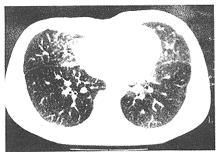

1.影像學檢查是診斷本病的主要手段。PAM在X線胸片上有如下的具體特徵:

(1)兩肺瀰漫分布的小結節影,直徑<1mm,密度高,邊緣清楚但形狀不規則。

(2)結節的密度和分布以中下肺野中內帶為顯著,病灶重疊時可顯示磨玻璃或片狀陰影。

(3)病灶可多年無明顯變化,也可稍增多,少數患者咳出結石而見病灶減少。

(4)後期可致肺不同程度纖維化、肺氣腫、肺大泡,最終導致肺動脈高壓、

慢性肺心病

(5)可並發自發性氣胸。放射學常根據病灶的範圍和密度將其分為輕中、重三度。

①輕度:胸片見中下肺野有廣泛瀰漫性細沙狀或星花樣鈣質斑點,斑點之間界限分明,上肺野清晰有鈣質纖維細紋理向上、外放射,肺門陰影正常。膈肌、肋膈角、心膈角和心影輪廓清晰可辨。此時多無臨床症狀常規實驗室檢查和肺功能檢查多屬正常。

②中度:自第二肋間以下表現為瀰漫性細沙樣鈣質斑點密布,以內帶和下肺野明顯,鈣質纖細紋理呈放射狀自肺門向上、向外伸展,鈣點尚未融合,左右心緣已部分遮蓋此時大多數僅有輕度臨床症狀,肺功能出現換氣功能障礙PaO2降低P(A-a)O2增大。

③重度:整個肺野皆為細沙狀或星花樣鈣質斑點密布,中下肺野尤為顯著,肺尖區因泡性肺氣腫關係而呈透明度增高,鈣質纖細紋理向肺尖和四周放射心臟外形、肋膈角、橫膈輪廓均消失,甚至一片模糊。肺門淋巴結不腫大。

少數病人X線胸片表現為瀰漫性高密度片狀陰影和網狀改變,需要通過胸部CT加以明確胸部CT和HRCT,能清楚地顯示出粟粒狀、高密度邊緣清楚的微結石陰影,也可發現小葉間隔增厚、纖維化和鄰近內臟受累情況。